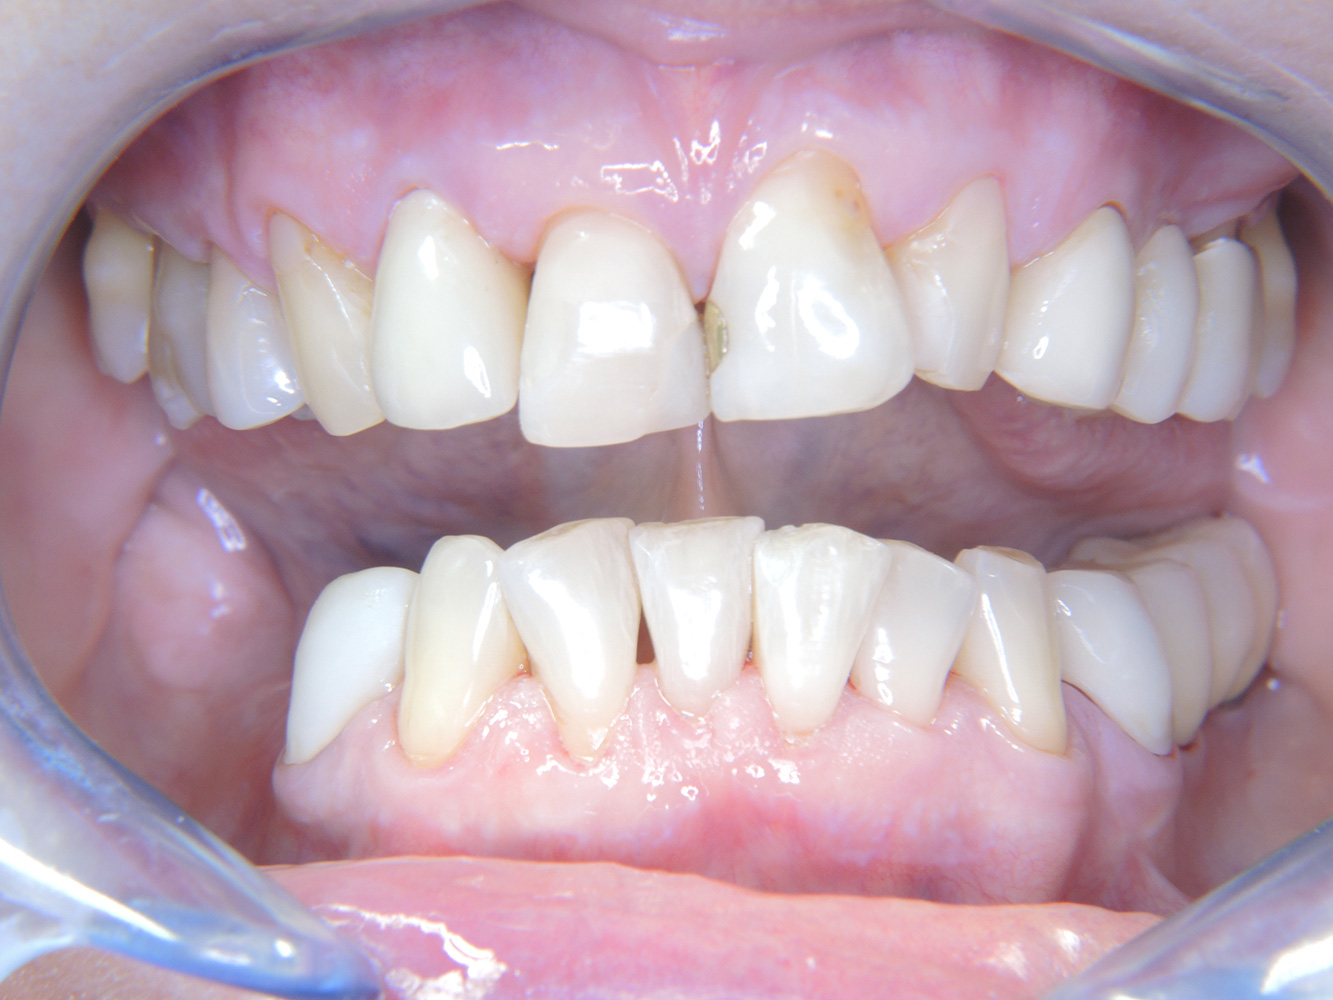

The healthy patient with early periodontal disease*

The 68-year-old patient has no general health conditions and is not taking any medication that may be relevant to her oral health, and her lifestyle does not pose any particular risk. The patient has two dental implants (3rd quadrant, for five years) and a previous case of periodontal disease (stage IV, grade B periodontitis) with tooth loss. Currently the periodontal conditions are stable. However, periodontitis significantly increases the biological complications of implantations and there is a risk of implant loss (21). Four recommendations can be determined for the prophylaxis session.

As the patient does not have any particular risk factors with specific dental implications, the requirements determined from her current state of oral health are crucial. Here, it is recommended that a thorough assessment of periodontal condition be carried out once a year. This will ensure that any potential progression of the previous periodontal disease or development of peri-implantitis can be responded to in good time.

Despite the stable conditions, it is also crucial for the instructive/motivational discussion to be conducted with this patient. Particular attention should be paid to teaching the patient how to care for the implants correctly. Here in particular, good at-home maintenance can have a significant impact on the long-term stability of oral and implant health.

In terms of instruments, specific procedures are required for use with implants. In order to preserve the surface of the implant while cleaning it effectively, it is essential to choose suitable powders and instruments such as the targeted use of air polishing devices with special periodontal tips. Which powder is most suitable can be determined according to the needs and risk. For example, in addition to the appropriate degree of abrasion, dietary requirements (including sugar-free, low-salt) may also be taken into account.

Because the patient has implants and a history of periodontal disease, she is at risk of developing peri-implantitis. It is therefore recommended that she attend a recall session every three to four months.

* with the kind permission of Dr G. Schmalz and Dr D. Ziebolz MSc.